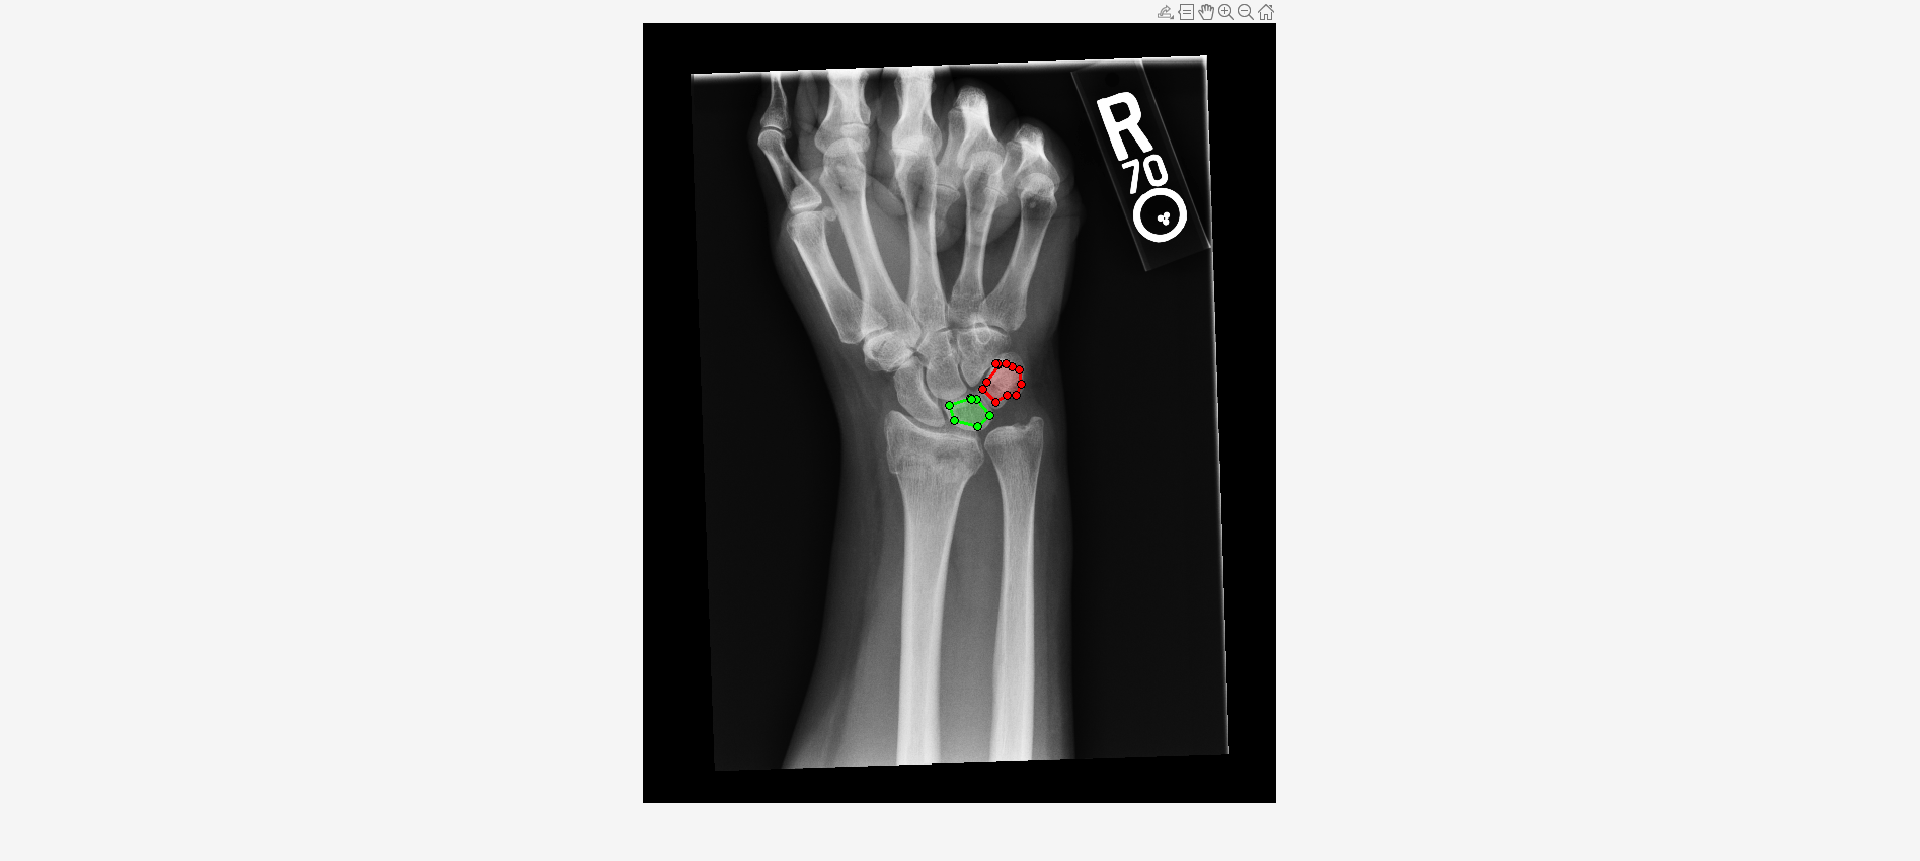

Load an X-ray image into the workspace as a medicalImage object. Visualize the image.

data = medicalImage("forearmXrayImage1.dcm");

I = data.Pixels;

figure

imshow(I,[])Draw two regions of interest (ROI) in the X-ray image. Create masks from the ROIs.

roi1 = drawassisted(Color="g"); roi2 = drawassisted(Color="r");

mask1 = createMask(roi1,I); mask2 = createMask(roi2,I);

Create an ROI label matrix, using different labels for the two ROIs. Create a medicalImage object of the ROI label data.

mask = zeros(size(I));

mask(mask1) = 1;

mask(mask2) = 2;

Compute shape features for both ROIs.

S = shapeFeatures(R)

S=2×24 table

LabelID VolumeMesh2D VolumeVoxelCount2D SurfaceAreaMesh2D SurfaceVolumeRatio2D Compactness1_2D Compactness2_2D SphericalDisproportion2D Sphericity2D Asphericity2D CentreOfMassShift2D Maximum3dDiameter2D MajorAxisLength2D MinorAxisLength2D LeastAxisLength2D Elongation2D Flatness2D VolumeDensityAABB_2D AreaDensityAABB_2D VolumeDensityAEE_2D AreaDensityAEE_2D VolumeDensityConvexHull2D AreaDensityConvexHull2D IntegratedIntensity2D

_______ ____________ __________________ _________________ ____________________ _______________ _______________ ________________________ ____________ _____________ ___________________ ___________________ _________________ _________________ _________________ ____________ __________ ____________________ __________________ ___________________ _________________ _________________________ _______________________ _____________________

"1" 54 54.427 135.84 2.5156 0.019243 0.13156 1.9662 0.5086 0.96618 0.18567 11.327 10.188 6.924 0 0.67962 0 0.63176 0.65158 NaN 0.91886 0.98182 0.99044 1.2498e+05

"2" 74 74.85 181.6 2.454 0.017061 0.10342 2.1304 0.46939 1.1304 0.24847 11.563 11.187 8.7535 0 0.78246 0 0.64598 0.66783 NaN 0.83862 0.93671 0.9552 1.8045e+05